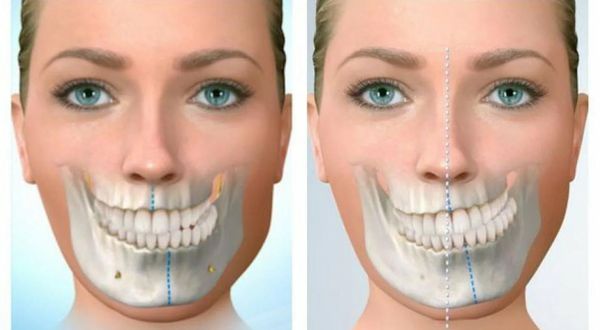

Асимметрия челюсти и лица (Jaw and face asymmetry) — это разные размеры и положения структур лицевого скелета, а также мягких тканей лица и челюсти.

Небольшая лицевая асимметрия есть почти у всех людей. Эта разница заметна по подбородку и носу, которые отклоняются в ту или иную сторону [2]. При измерении пропорции челюстей с помощью компьютерной томографии и телерентгенографии (рентген-исследования черепа) отмечается их небольшое отличие: менее 2–3 мм [12]. Функция жевания и речи остаётся относительно хорошей.

Бывает и патологическая асимметрия, которая нарушает функцию челюсти. При обследовании и измерении её симметрии видны значительные отклонения от условной нормы: более 2–3 мм [12].

1. Смещение подбородка в разные стороны (вправо, влево, вперёд или назад) относительно центра лица. Оно может быть разной степени выраженности, но обычно его тяжело не заметить.

Смещение подбородка [11]